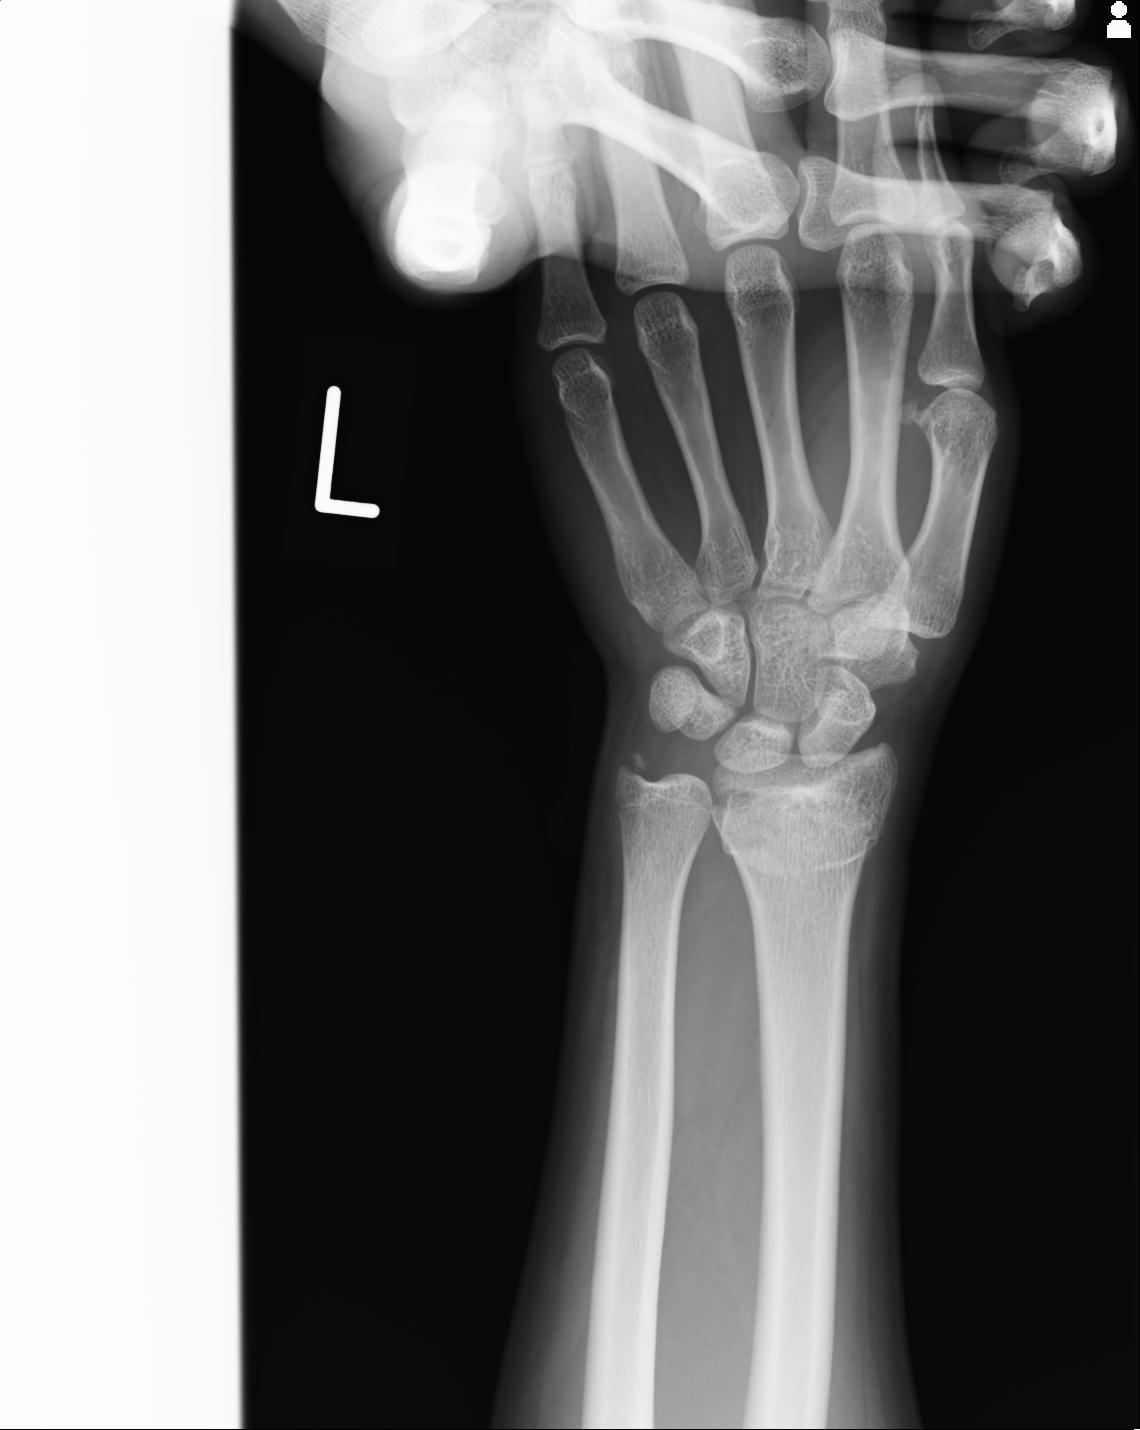

46666 1/23 両股正面+軸と右手関節 2R 76歳女性 右橈骨遠位端

46666 1/28 両股正面+軸と 1/26 右手関節 2R 76歳女性 右転子部骨折